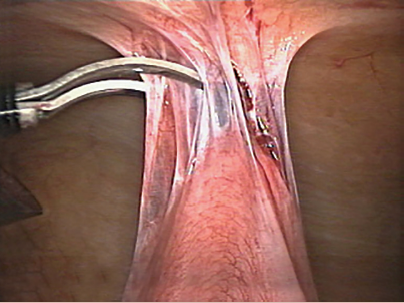

Los hallazgos de la laparoscopia diagnóstica realizada en la paciente el 10 de agosto de 2018, fueron de adherencias postoperatorias (figura 3) que impedían el libre flujo intestinal, con la realización de adherenciolisis, entendiéndose por adherencias postoperatorias cualquiera de las cicatrices postraumáticas (postoperatorias) entre 2 superficies peritoneales contiguas que normalmente están desunidas; después de intervenciones quirúrgicas que dan lugar a un trauma peritoneal, el tejido de la cicatriz anormal entre las superficies peritoneales que son normalmente libres, lo que resulta en la formación de adherencias definitivas13 y que son responsables del 75% de las causas de obstrucción intestinal; su manejo quirúrgico se centra en la separación gentil de las adherencias entre las asas intestinales, a lo que se denomina adherenciolisis. Por ello, en la especie, la obstrucción intestinal secundaria a la formación de las adherencias postquirúrgicas, no puede ser tenida como ocasionada por mala práctica del cirujano a cargo, sino que se trató de una respuesta propia del organismo de la paciente, sin injerencia del cirujano y entendiéndose como un riesgo inherente al procedimiento de plastía de pared realizado en el hospital.